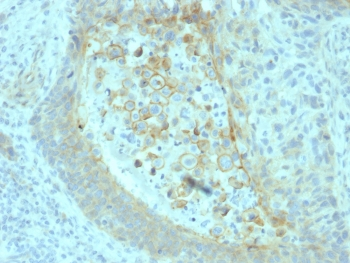

IHC staining of FFPE human prostate carcinoma with CD73 antibody (clone NT5E/2545). HIER: boil tissue sections in pH9 10mM Tris with 1mM EDTA for 10-20 min and allow to cool before testing.

IHC staining of FFPE human pancreatic carcinoma with CD73 antibody (clone NT5E/2545). HIER: boil tissue sections in pH9 10mM Tris with 1mM EDTA for 10-20 min and allow to cool before testing.